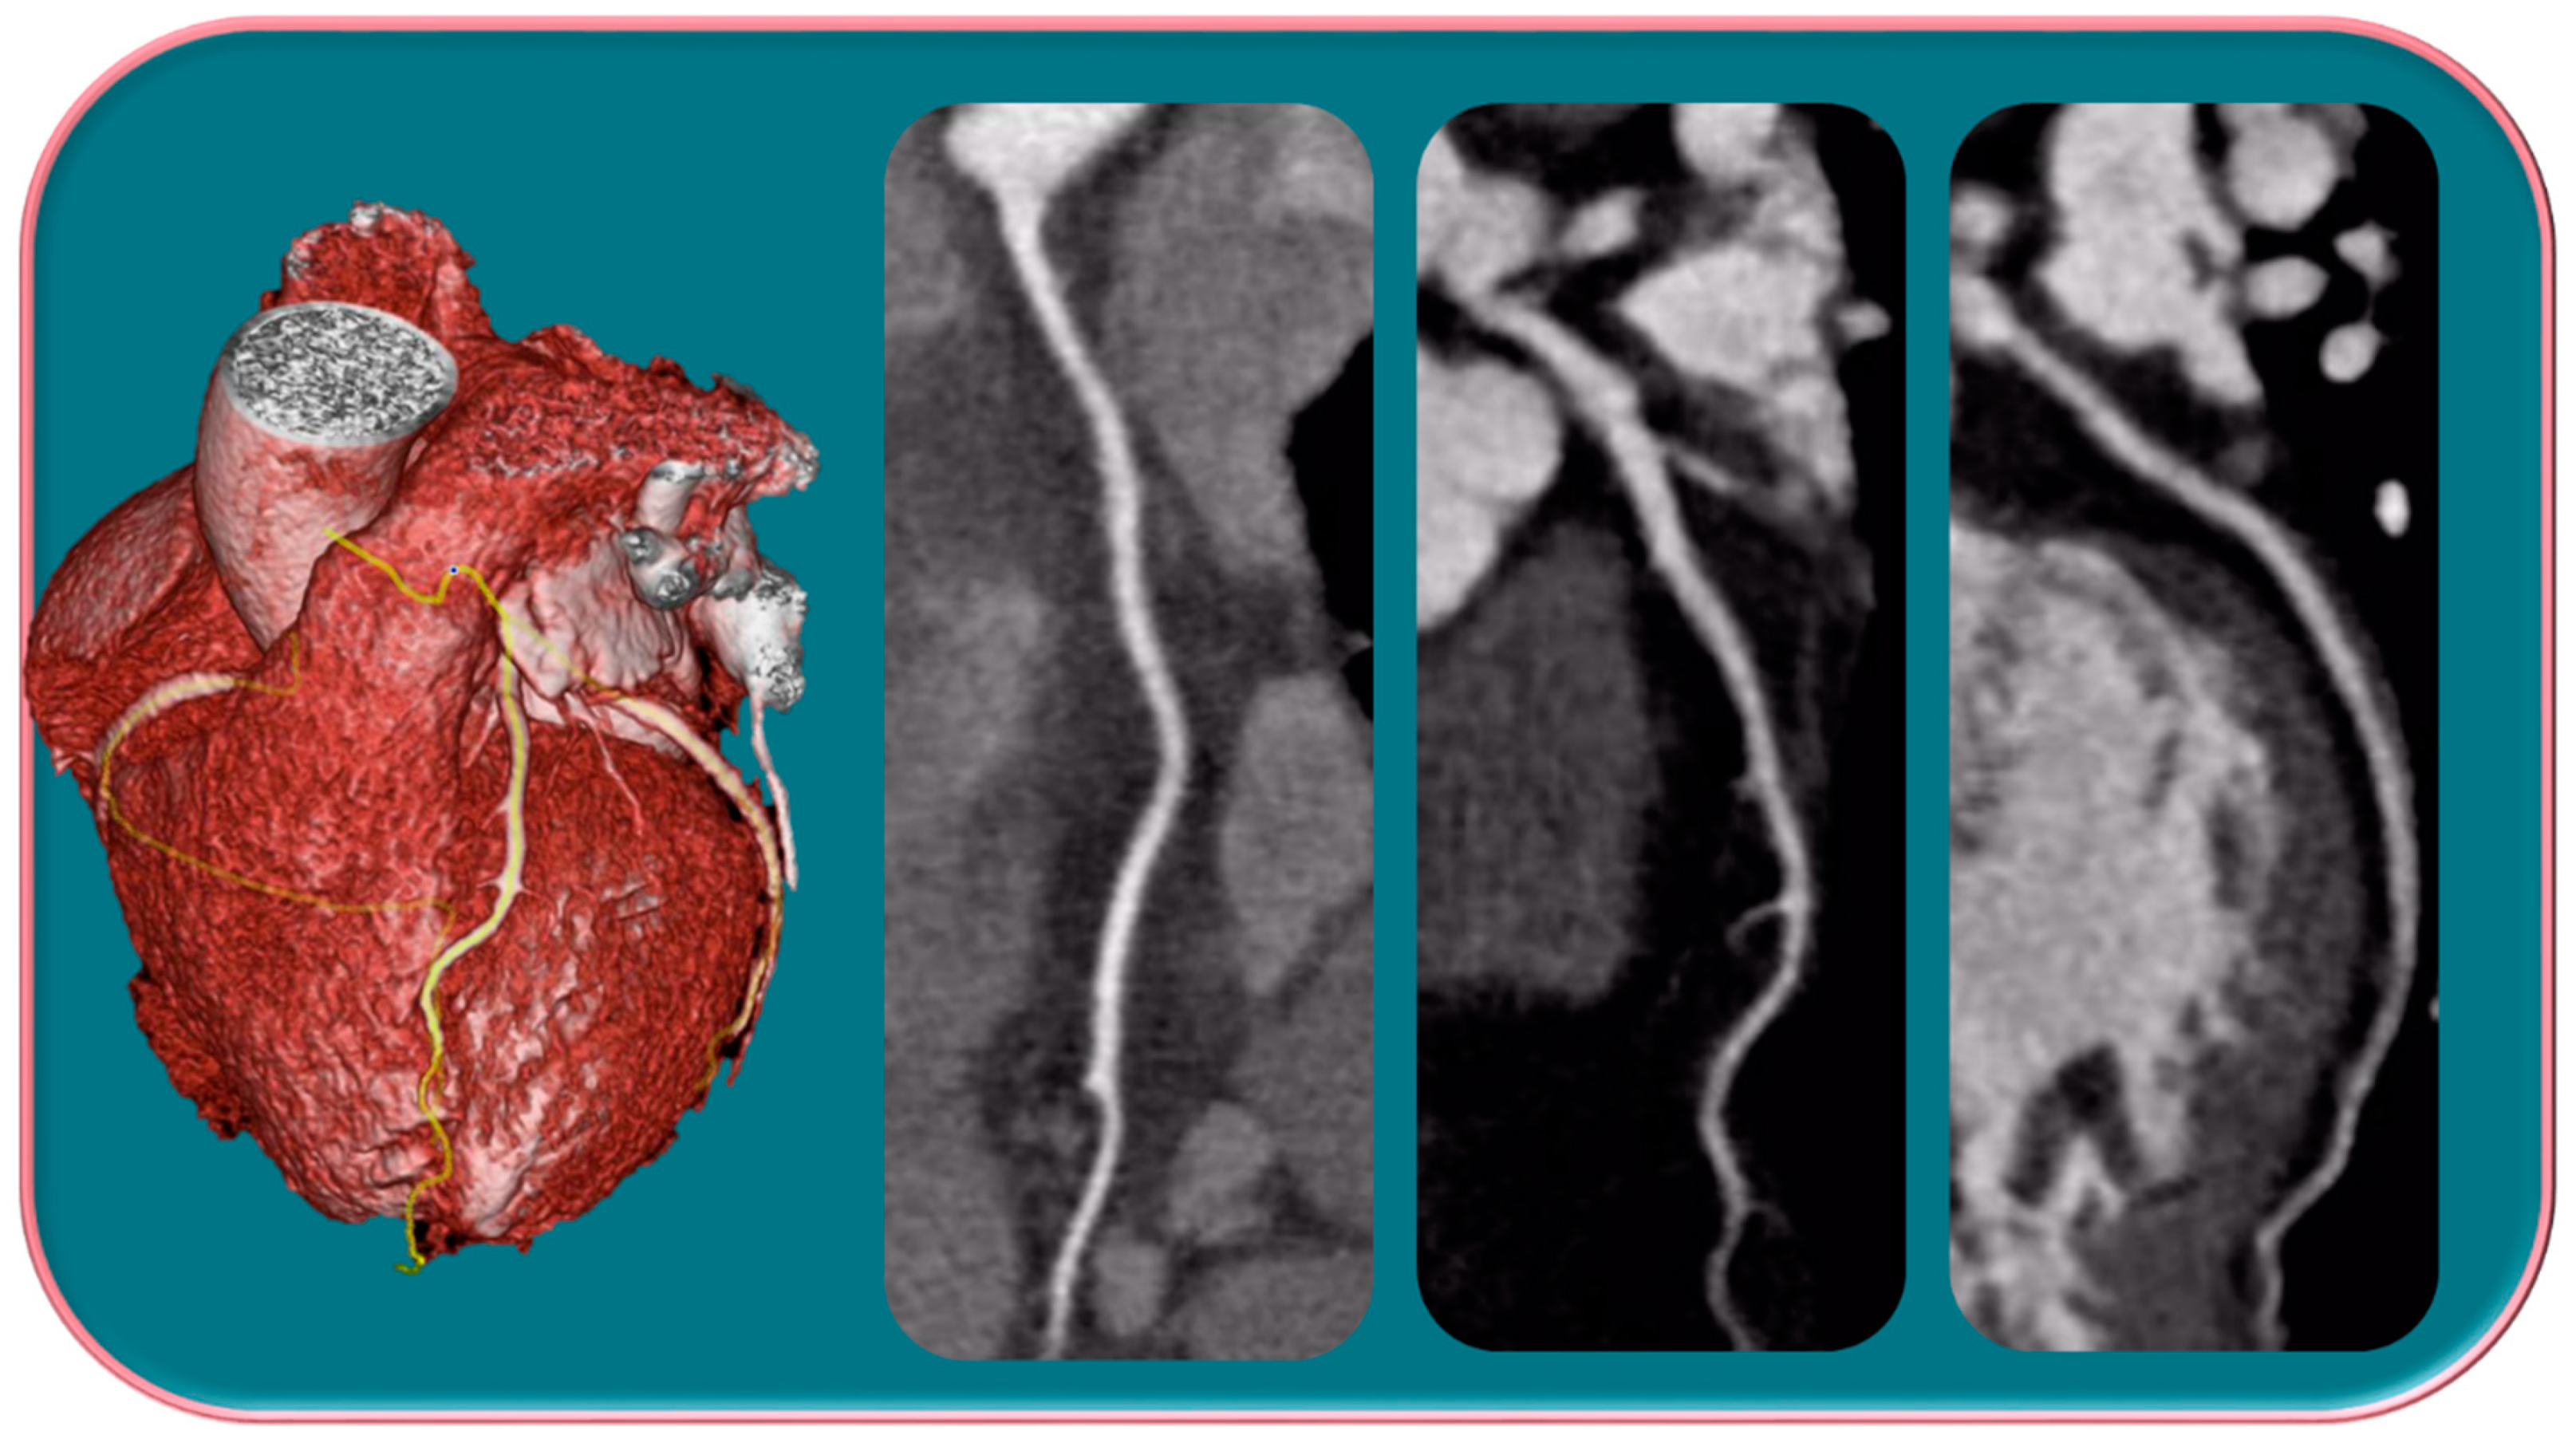

Several studies have shown that there is an over-representation of women with myocardial infarction with unobstructed coronary arteries (MINOCA) (Figure 2) [49,50,51].

Figure 2.

Female, 65-years-old, with typical angina, treated for hypertension and dyslipidemia. The patient was first categorized as intermediate-PPT risk of having CAD, for which CCTA was performed. The CCTA exam showed a regular coronary tree. Different trials have demonstrated that women show more frequent anginal symptoms than men, often with a higher risk profile, although a lower overall burden of CAD, a higher prevalence of NOCAD, and a frequent insufficient ischemia have been highlighted.

The mechanisms underlying MINOCA most commonly observed in women include coronary microvascular dysfunction and plaque erosions. Identification of the underlying etiology of MINOCA is, therefore, critical for proper risk stratification and with regard to treatment [52,53].